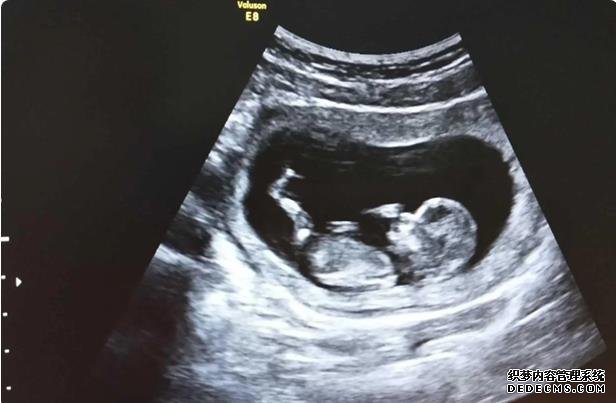

在胚胎移植后的14天,女方需要去医院进行血液HCG检测,以确定移植胚胎是否着床,即是否怀孕,如果怀孕,就需要做B超检查,这部分的费用以医院收费为准。

实际上孕妇长时间保持一个姿势,无论是站着还是躺着,胎儿都不会喜欢,孕妇可以根据实际情况来调整自己的姿势,可以每隔一段时间就调整一下姿势,这样是有利于胎儿发育的,注意尽量不要长期保持一个姿势不动。孕妇在日常生活中要注意休息,同时也要注意运动,长时间的卧床和久站都是不好的,要注意劳逸结合,这样才能维持良好的胎盘血供。